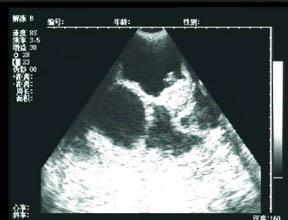

42天时去做第一次b超,就发现了有一点不对的地方,就是孕囊在左宫角那里,也许很多人,还不太了解,就是还没有到最里面,宝宝就在那里扎根了,如果乐观长长就进去了,如果不乐观,医生说就证明自己怀孕过。当然医生也不能说的那么绝对,就说明天再来一次,有专家来,再给看看。谁知这一来二去做了4次b超,让本来担心的小小,越来越担心了,心情也不再好了,这几天就哭了好几回,医生说先回家观察,只要不出血,就没有什么问题,再大一点再来观察,最主要的就是心情了。